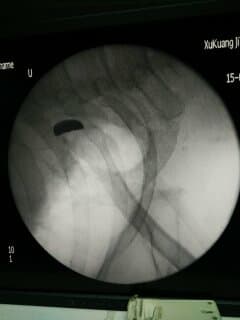

2:05,救护车到达医院本部,小姜被紧急转入ICU。心脏外科缪丙荣主任医师和李建明医师迅速到位,联合ICU李娜副主任医师,陈娇护师会诊抢救,于3:20实施心包穿刺术,引流出血性液体共计400毫升,随着这些积血的排出,小姜的心脏负担明显减轻,循环功能逐渐改善,暂时脱离了生命危险,但病情依然危重,且处于意识不清的状态。因此,在充分评估了小姜的病情和身体状况后,团队决定继续执行原有的治疗方案,同时加强监护和观察,确保任何细微的变化都能被及时发现并妥善处理。

13:45,患者被转运至手术室,麻醉科王凯副主任医师发现患者血压不能测知,团队判断患者发生心脏骤停,面对这一紧急情况,在王蔚主任医师的带领下,整个手术室迅速运转起来,各司其职:侍巍副主任医师立即胸外心脏按压、李建明医师消毒铺单,器械护士各种台上设备到位,王蔚主任医师迅速胸骨正中切口开胸,所见胸骨横断骨折,心包饱满呈蓝紫色;切开心包后,可见大量血液涌出,立即直接给予心脏按摩,并立即采取了电除颤复律措施;此时,心脏恢复跳动,心包内大量积血被吸入血液回收机中。

“通过迅速探查,我们发现患者右心耳根部近上腔静脉处有一个1公分左右的裂口。”王蔚描述,这是导致心包填塞和循环不稳定的直接原因。他立即对患者右心耳根部的破裂口进行了精细、迅速的缝合修补,有效止住了活动性出血。从开胸到控制出血,总共不到20分钟;看着年轻的心脏恢复有力地跳动,来自王凯副主任医师的一句“瞳孔对光反射良好”,让大家总算松了一口气。